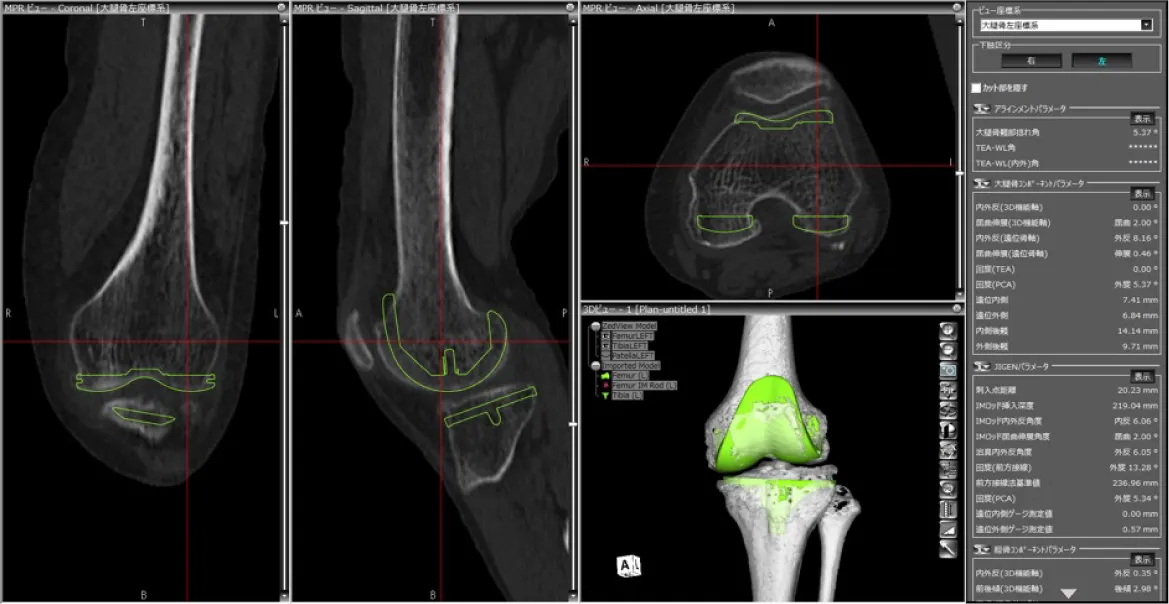

当院では術前のCT画像をコンピューターに取り込み、特別なソフトウエアを使用して、手術を受けられる方個々の骨の形に合うように手術前計画を立てています。

さらにその計画を元に正確な手術ができるよう、最新のARポータブルナビゲーションを使用して手術を行っております。

この手術法により、より正確な人工関節の設置が可能となり、より長期間の関節機能維持と膝の痛みの改善が期待されます。

3次元術前計画